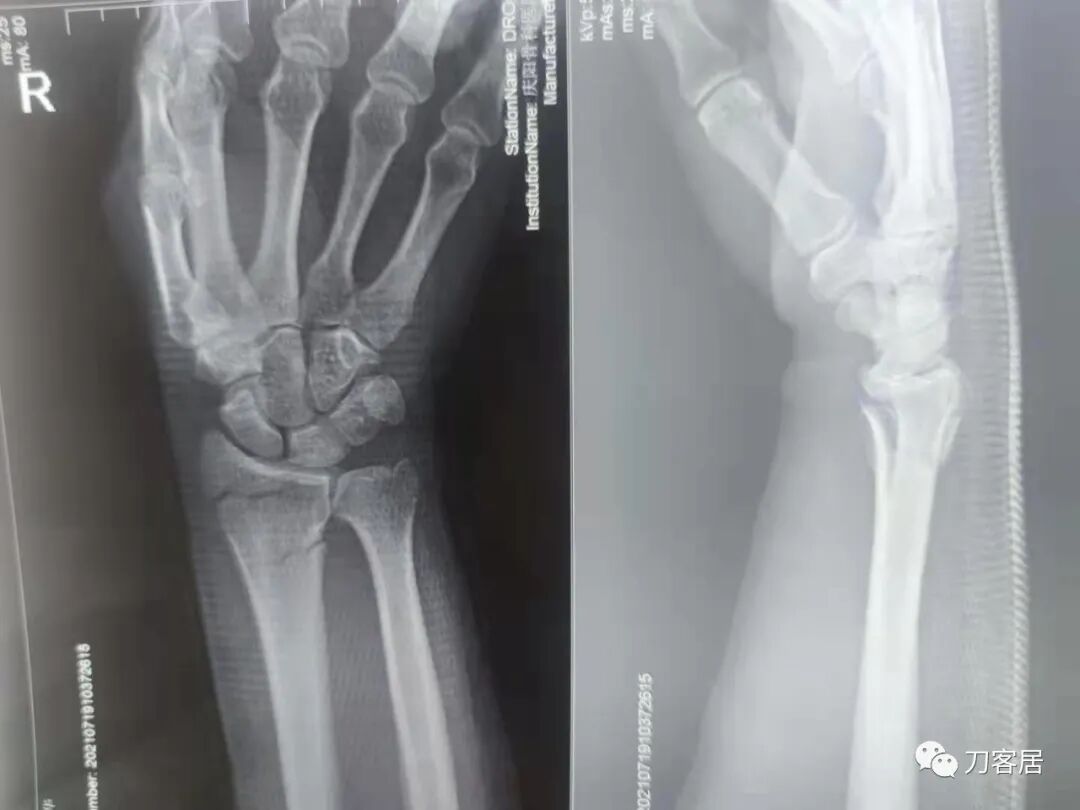

下面是这个6岁孩子,尺桡骨远端双骨折的术前及术后片子和外观照片。

2.  这个骨折处理起来也很简单,单纯的打石膏托或者中医的小夹板,或者正规的包括腕关节和肘关节的管型石膏外固定4周即可治愈该骨折。实在不行,如果这个孩子比较听话,不太调皮的话,用一本书,一个三角巾悬吊固定4周,都可以治愈该骨折。但是给这个患者用外固定架做了手术,而且桡骨远端的几颗克氏针距离骨折线太近,其中一枚克氏针进入到骨折间隙内。从这个术中图片来看,术者的外固定手术技术也有待于进一步的提高。毕竟术者应该还很年轻。从X线片来看,前臂及手的尺侧有不透光影,应该还使用了外固定石膏绷带托,而且我猜测应该是高分子的石膏绷带托,这个是纯属猜测,不一定是对的,不过如何解释前臂尺侧的不透光影呢?如果真是用了石膏绷带外固定的话,那为啥要做手术呢?外固定架术后就不该再用石膏绷带托辅助了。

这个病例,6岁的孩子,尺桡骨骨折在同一个平面,且都为小斜行骨折,不是螺旋形,不是粉碎性,不是成角移位性,属于稳定性尺桡骨双骨折,根本就没有任何手术的适应症。